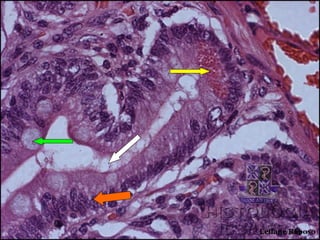

Monitoria de Histologia II

• Qual o corte histológico?

• Qual a estrutura apontada pela seta branca?

• Qual a célula apontada pela seta amarela? Qual

sua função?

• Qual a célula apontada pela seta laranja? Qual

• Qual a célula apontada pela seta verde? Qual sua

função?